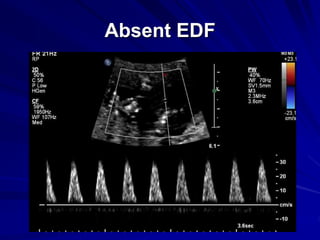

Reduced EDF

Absent EDF